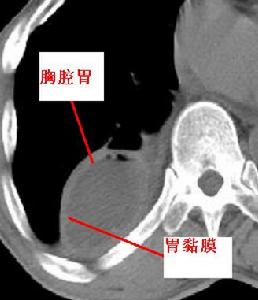

胃黏膜酗酒傷身的道理眾所周知,但酒精對大腦的損害卻很少引起重視。近年來,酒精性腦萎縮患者有增多趨勢。酒精之所以損害健康的腦組織,是因為乙醇能直接通過胃黏膜吸收入血,並很快通過血腦屏障進入大腦。酒精是一種親神經物質,具有神經毒性作用,能直接殺傷腦細胞,使之溶解、消亡、減少。長期飲酒者腦細胞死亡速度會越發加快,腦萎縮也會越來越嚴重。伴隨腦血流量的減少,腦內葡萄糖代謝率、腦神經細胞活性均減低,大腦功能隨之衰退。

乙醇酒精性腦萎縮常引起營養障礙,主要是由於酒精進入體內首先刺激胃黏膜,對其造成損傷並引起營養物質的吸收障礙及維生素的缺乏而出現慢性胃炎及營養不良,當患者以酒代餐甚至連續多日不進食時導致營養不良,硫胺攝入不足和吸收不良等,從而引起腦代謝障礙,甚者出現急性韋尼克氏腦病發作。故患者發病後應及時到醫院治療,並保證營養供給,可減少酒精性腦病的發生。